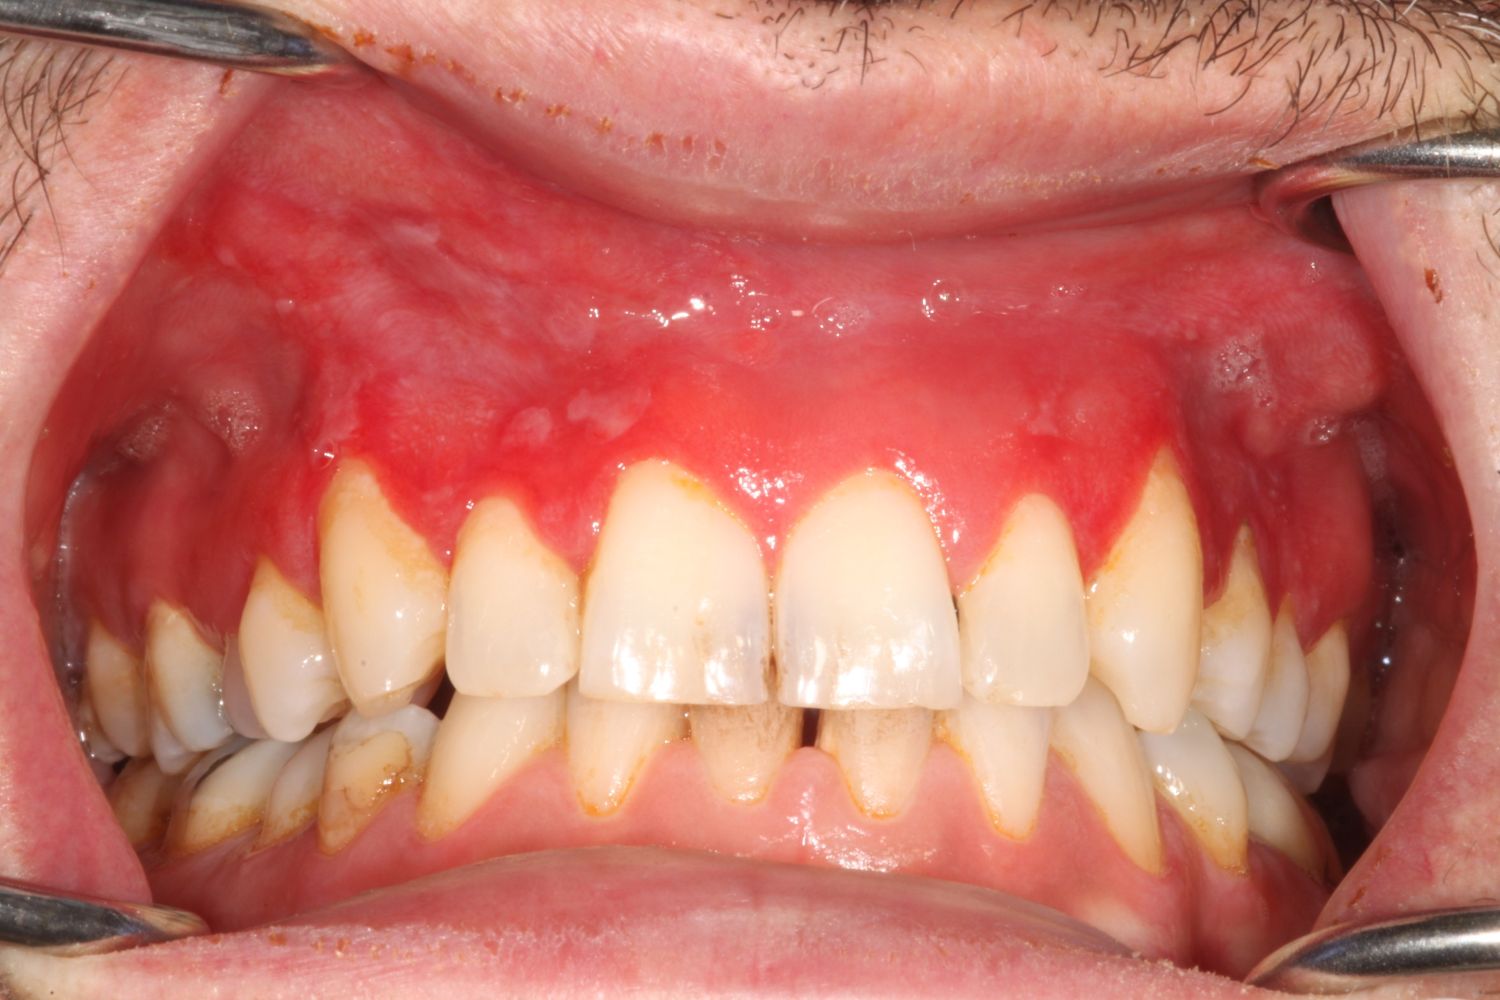

Brown snus users often develop wrinkled mucosa with a white-colored thickening where the snus is placed. Some white snus users, on the other hand, have painful and distinctly red-colored changes to the gums. In certain cases, ulcers can also appear where the white snus is placed against the mucosa.

"We're more concerned about these lesions. They're completely different, with redness and thinning of the mucous membrane. Tissue samples have revealed severe inflammation, and we recommend that users stop using snus immediately if they develop problems or notice changes," says dr Gita Gale, specialist dentist and one of the researchers behind the study.

The lesions associated with white snus use also seem to heal more slowly. Among brown snus users, once they stop using it, their gums usually recover within a few weeks. With white snus, however, the damage has been seen to last for several months, even as much as a year.